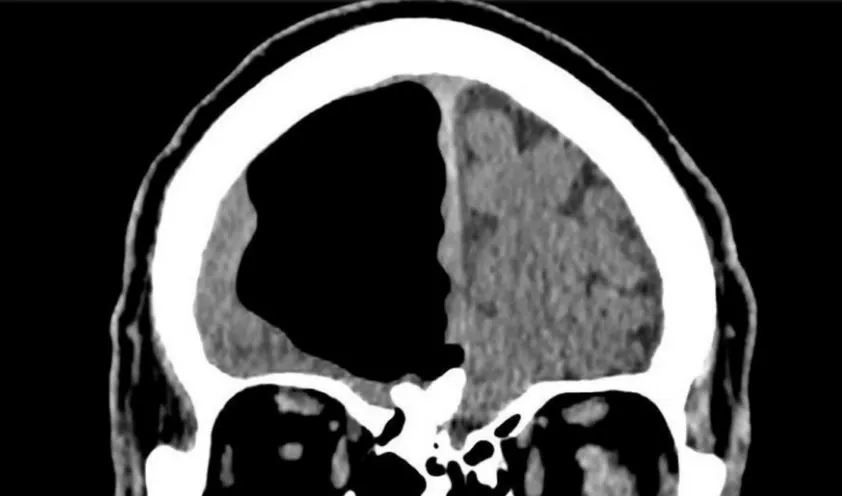

Phim chụp MRI cho thấy một phần não của ông cụ bỗng dưng biến mất kỳ lạ. Ảnh: BMJ Case Reports

Cuối cùng, họ cho ông chụp CT và MRI não và họ khá sốc khi phát hiện ra một sự việc khác kỳ lạ. Thùy não trái của ông lão hoàn toàn trống không.

Đây là một trong những hiện tượng y khoa hiếm thấy trên thế giới. Ảnh: BMJ Case Reports

Chẩn đoán rằng người đàn ông có thể đã bị khí sọ, một hiện tượng tụ khí trong não thường xảy ra đối với những bệnh nhân phẫu thuật não. Nó cũng có thể xảy ra sau khi bị nhiễm trùng xoang, chấn thương đầu hoặc mặt nhưng thường những túi khí nhỏ chứ không to như vậy.

Trong trường hợp này, lỗ hổng trong não bệnh nhân đo được khoảng 8,9 cm, chiếm gần trọn thùy não trái.